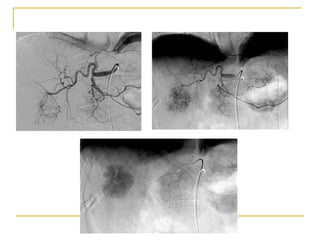

Arterial therapy

cTACE-conventional transarterial chemoembolization Administration of chemotherapeutic agent mixed with ethiodal prior to arterial obstruction with embolic beads. Ethiodal is selectively retained within the tumor and prolongs chemotherapy dwell time.

Mechanism of cTACE

HCC exhibits intense new-angiogenic activity with blood supply progressing from the portal vein to the hepatic artery

Chemotherapy delivered in high concentration enhances coagulative tumor necrosis

Arterial obstruction results in ischemic tumor necrosis with a high rate of objective response

Perfusion to uninvolved liver is maintained by the portal vein permitting selective targeting of tumor